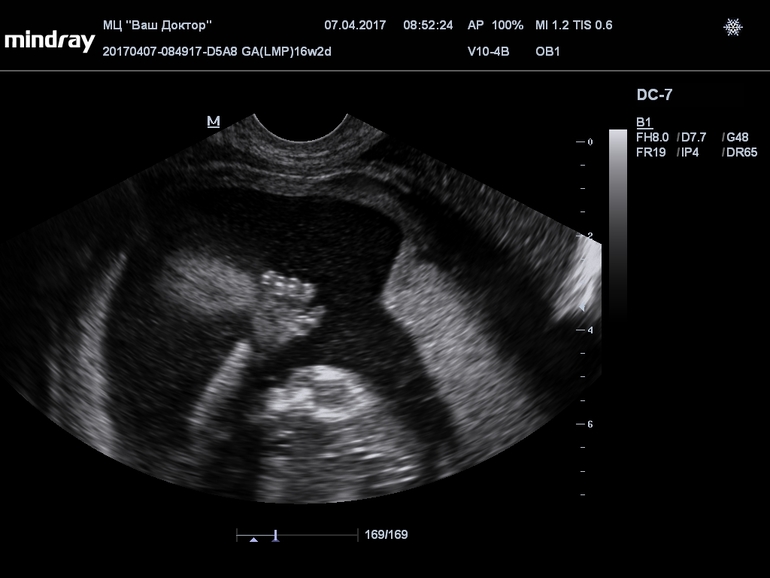

Девчат, только что со скрининга! Не могу не поделиться этим забавным кадром :) малыш дал пять :D

По м срок 12+4, по скрининг поставили 12+1. Все в норме. И это мое самое первое УЗИ за всю беременность, наконец-то впервые услышала сердце и вообще...это непередаваемо, смотреть как он там плавает, когда его тормошили ))) пальчик сосет. Такой малютка. Папа был с нами, говорит сидел там как обалдевший ))))

ну это срок потому что 16 недель. кстати, на этом сроке самый удачный диск с записью УЗИ. Потом малыши уже не помещаются целиком на экране...